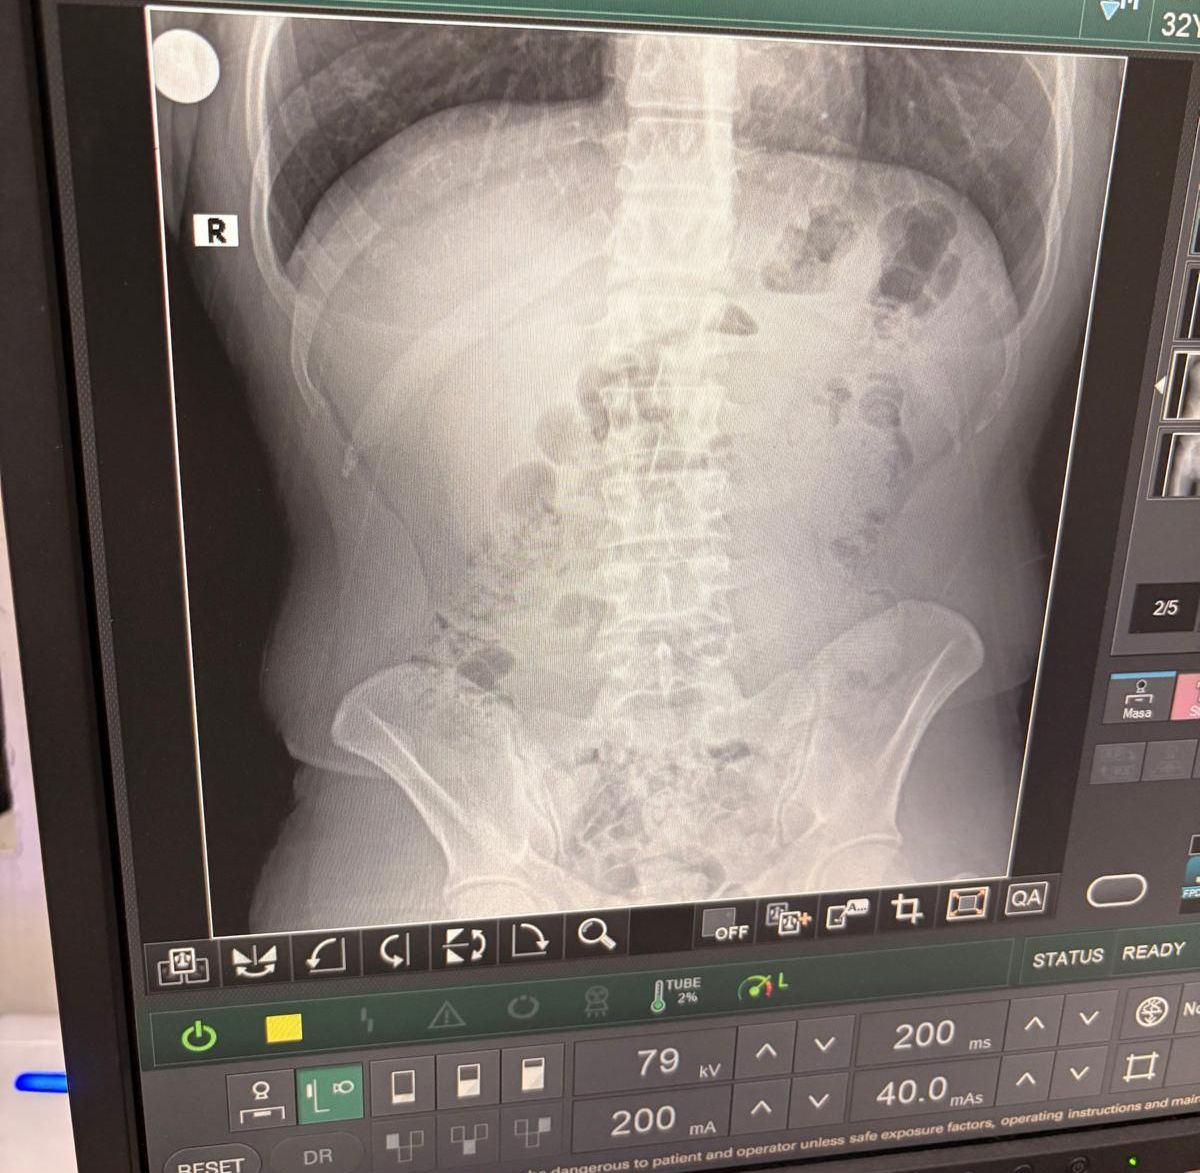

Röntgen Filmleri Gerçeği Ortaya Çıkardı

Uyuşturucunun paketlenme şekli ekiplerin dikkatini çekti. Şahıslar hastaneye sevk edilerek detaylı kontrollerden geçirildi. Röntgen sonuçlarında, şüphelilerin mide ve bağırsaklarında çok sayıda kapsül olduğu tespit edildi.

Kontrollü tıbbi müdahalenin ardından, toplam 140 kapsül metamfetamin çıkarıldı.